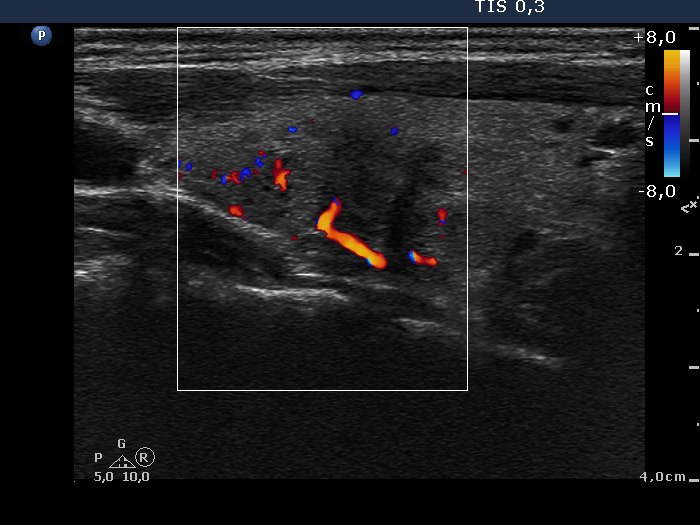

Left lobe, another longitudinal scan, color Doppler mode.